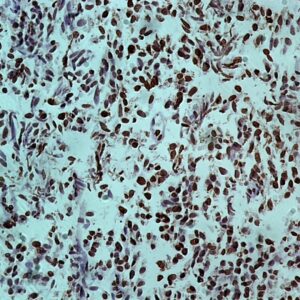

miRNA Probes

BioGenex has pioneered the development of miRNA research and diagnostics tools with leading-edge products. Currently, we offer over 240 ready-to-use (RTU) Super Sensitive™ Nucleic Acid (SSNA) miRNA ISH probes for accurate and early tumor diagnosis. These probes are sensitive enough to detect low-abundant miRNA(s) that are often required to identify biomarkers. They have a high melting temperature enabling stringent washes to remove non-specific binding. BioGenex miRNA probes are dual-end labeled with an anti-fluorophore to amplify the signal and yield clean and intense staining.